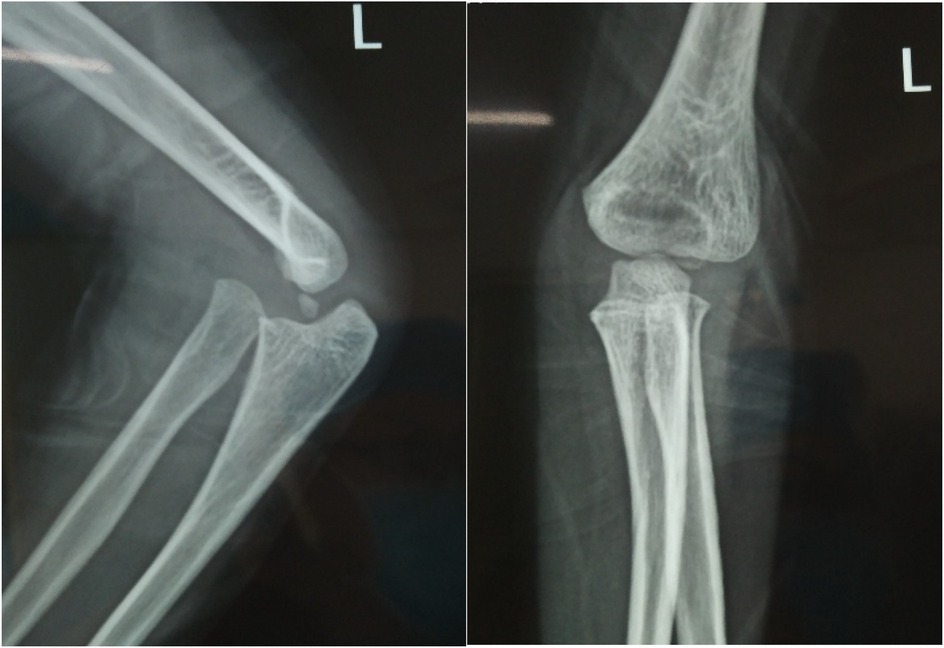

Objective: To investigate and analyze the application value of elbow arthrography in the treatment of chronic radial head dislocation in children. Methods: From January 2014 to January 2017, 15 children with chronic anterior radial head dislocation were treated (11 boys, 4 girls; average age 9 years, range 3-11 years). Intraoperative elbow arthrography was performed to assess the position of the radial head relative to the joint capsule. The nature of the dislocation was confirmed by opening the joint capsule to directly observe the relationship between the radial head and capitellum, as well as the morphology of the radial head. Reduction of the radial head was achieved via proximal ulnar osteotomy, and fixation was performed using a plate and screws with or without Kirschner wires (K-wires). Results: Elbow arthrography showed the radial head was located within the joint capsule in 12 cases and outside the capsule in 3 cases. Among the cases: All 8 congenital dislocations had the radial head within the joint capsule. Of the 7 traumatic dislocations, 4 had the radial head within the capsule and 3 outside. Direct inspection after capsulotomy confirmed the arthrography findings and revealed characteristic morphological differences. In congenital dislocations, there was no scar tissue between the radial head and capitellum, and the radial head fovea was shallow and flat. In traumatic dislocations, obvious scar tissue was present between the radial head and capitellum, and the radial head fovea was distinct. Follow-up ranged from 9 months to 4 years (average 2 years 5 months). Postoperative radiographs showed no cases of radial head re-dislocation or subluxation. Postoperative elbow range of motion improved in all patients, with no reports of pain or functional instability. Conclusion: Elbow arthrography serves as a valuable adjunct for differentiating between congenital and traumatic radial head dislocations, thereby informing both surgical strategy and the decision for supplemental fixation. When stable bony alignment is achieved, proximal ulnar osteotomy without annular ligament reconstruction represents an effective management strategy for chronic radial head dislocation in children.